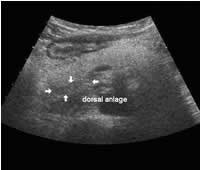

While an anatomic atlas is helpful for obtaining a detailed description of the morphology of the pancreas, I will also discuss the anatomic landmarks that are important from the sonographer's point of view. The pancreas is located in the epigastrium and has an oblong shape, oriented transversally across the midline. The main parts of the pancreas are the head with the uncinate process and the dorsal bud to the right, the body in the middle and the tail to the far left. The longest part of the pancreas is located to the left of the midline, with the tail near the splenic hilum usually slightly above the head. There are no clear demarcations between the different areas, though sometimes the dorsal bud of the head is darker, with sharp delineation compared to the rest of the pancreas.

The following study describes anatomical landmarks in the ordinary pancreas of a thin patient:

Transverse planes in caudal direction:

Bright pancreas, clear dark dorsal bud (anlage):